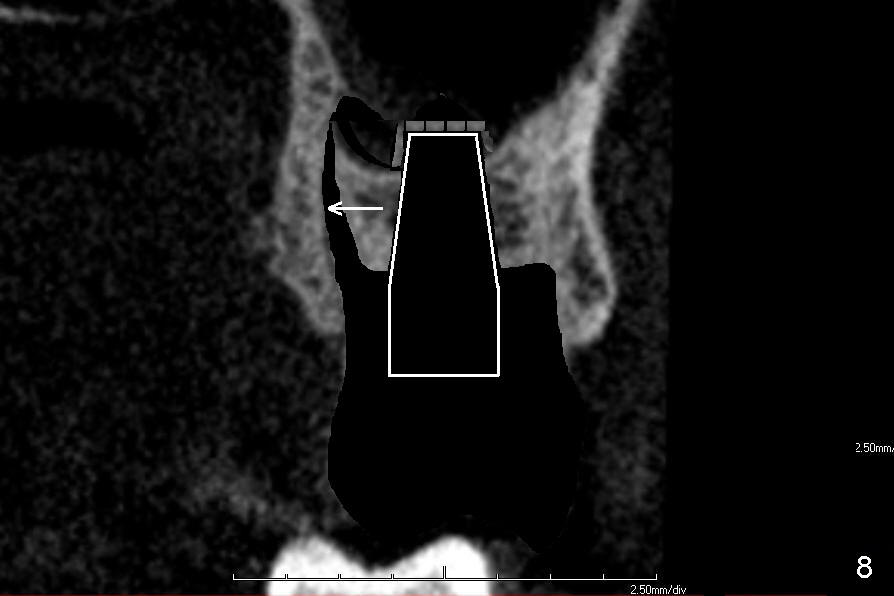

If the septum is small or destroyed by the infection, an implant will be placed in the palatal root (Fig.5), since it is the biggest among these 3 roots (Fig.2). The advantage is that the implant is longer than that placed in the septum (Fig.8). The drawback is that the implant is off center (Fig.5, as compared to that placed in the septum (Fig.8)). The implant placed in the palatal socket is relatively small in diameter. The whole socket will not be occupied by the implant. Collagen membrane will be used to help close the socket as well as bone graft.

If the septum is not so bad in size, osteotomes (RT series) will be used to expand it (to obliterate 3 sockets) and finish sinus lift to increase implant length if bone is not too hard to manipulate (Fig.6,7). Osteotomy is finished by using proper size and length of taps. Finally a large, but relatively short implant is placed in the septum (Fig.8). Arrowheads in Fig.6-8 indicate that as osteotomes are driven in sequentially (Fig.6,7 white box) and the implant is placed (Fig.8), bone segment may be moved palatally to obliterate the palatal socket gradually.